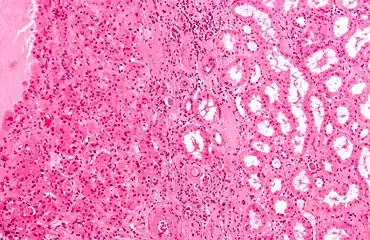

Micrograph of a renal oncocytoma, a type of benign kidney tumour. H&E stain.